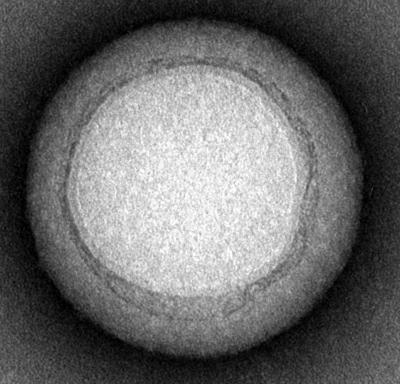

Each nanosponge has a diameter of approximately 85 nanometers and is made of a biocompatible polymer core wrapped in segments of red blood cells membranes.

Zhang's team separates the red blood cells from a small sample of blood using a centrifuge and then puts the cells into a solution that causes them to swell and burst, releasing hemoglobin and leaving RBC skins behind. The skins are then mixed with the ball-shaped nanoparticles until they are coated with a red blood cell membrane.

Just one red blood cell membrane can make thousands of nanosponges, which are 3,000 times smaller than a red blood cell. With a single dose, this army of nanosponges floods the blood stream, outnumbering red blood cells and intercepting toxins.